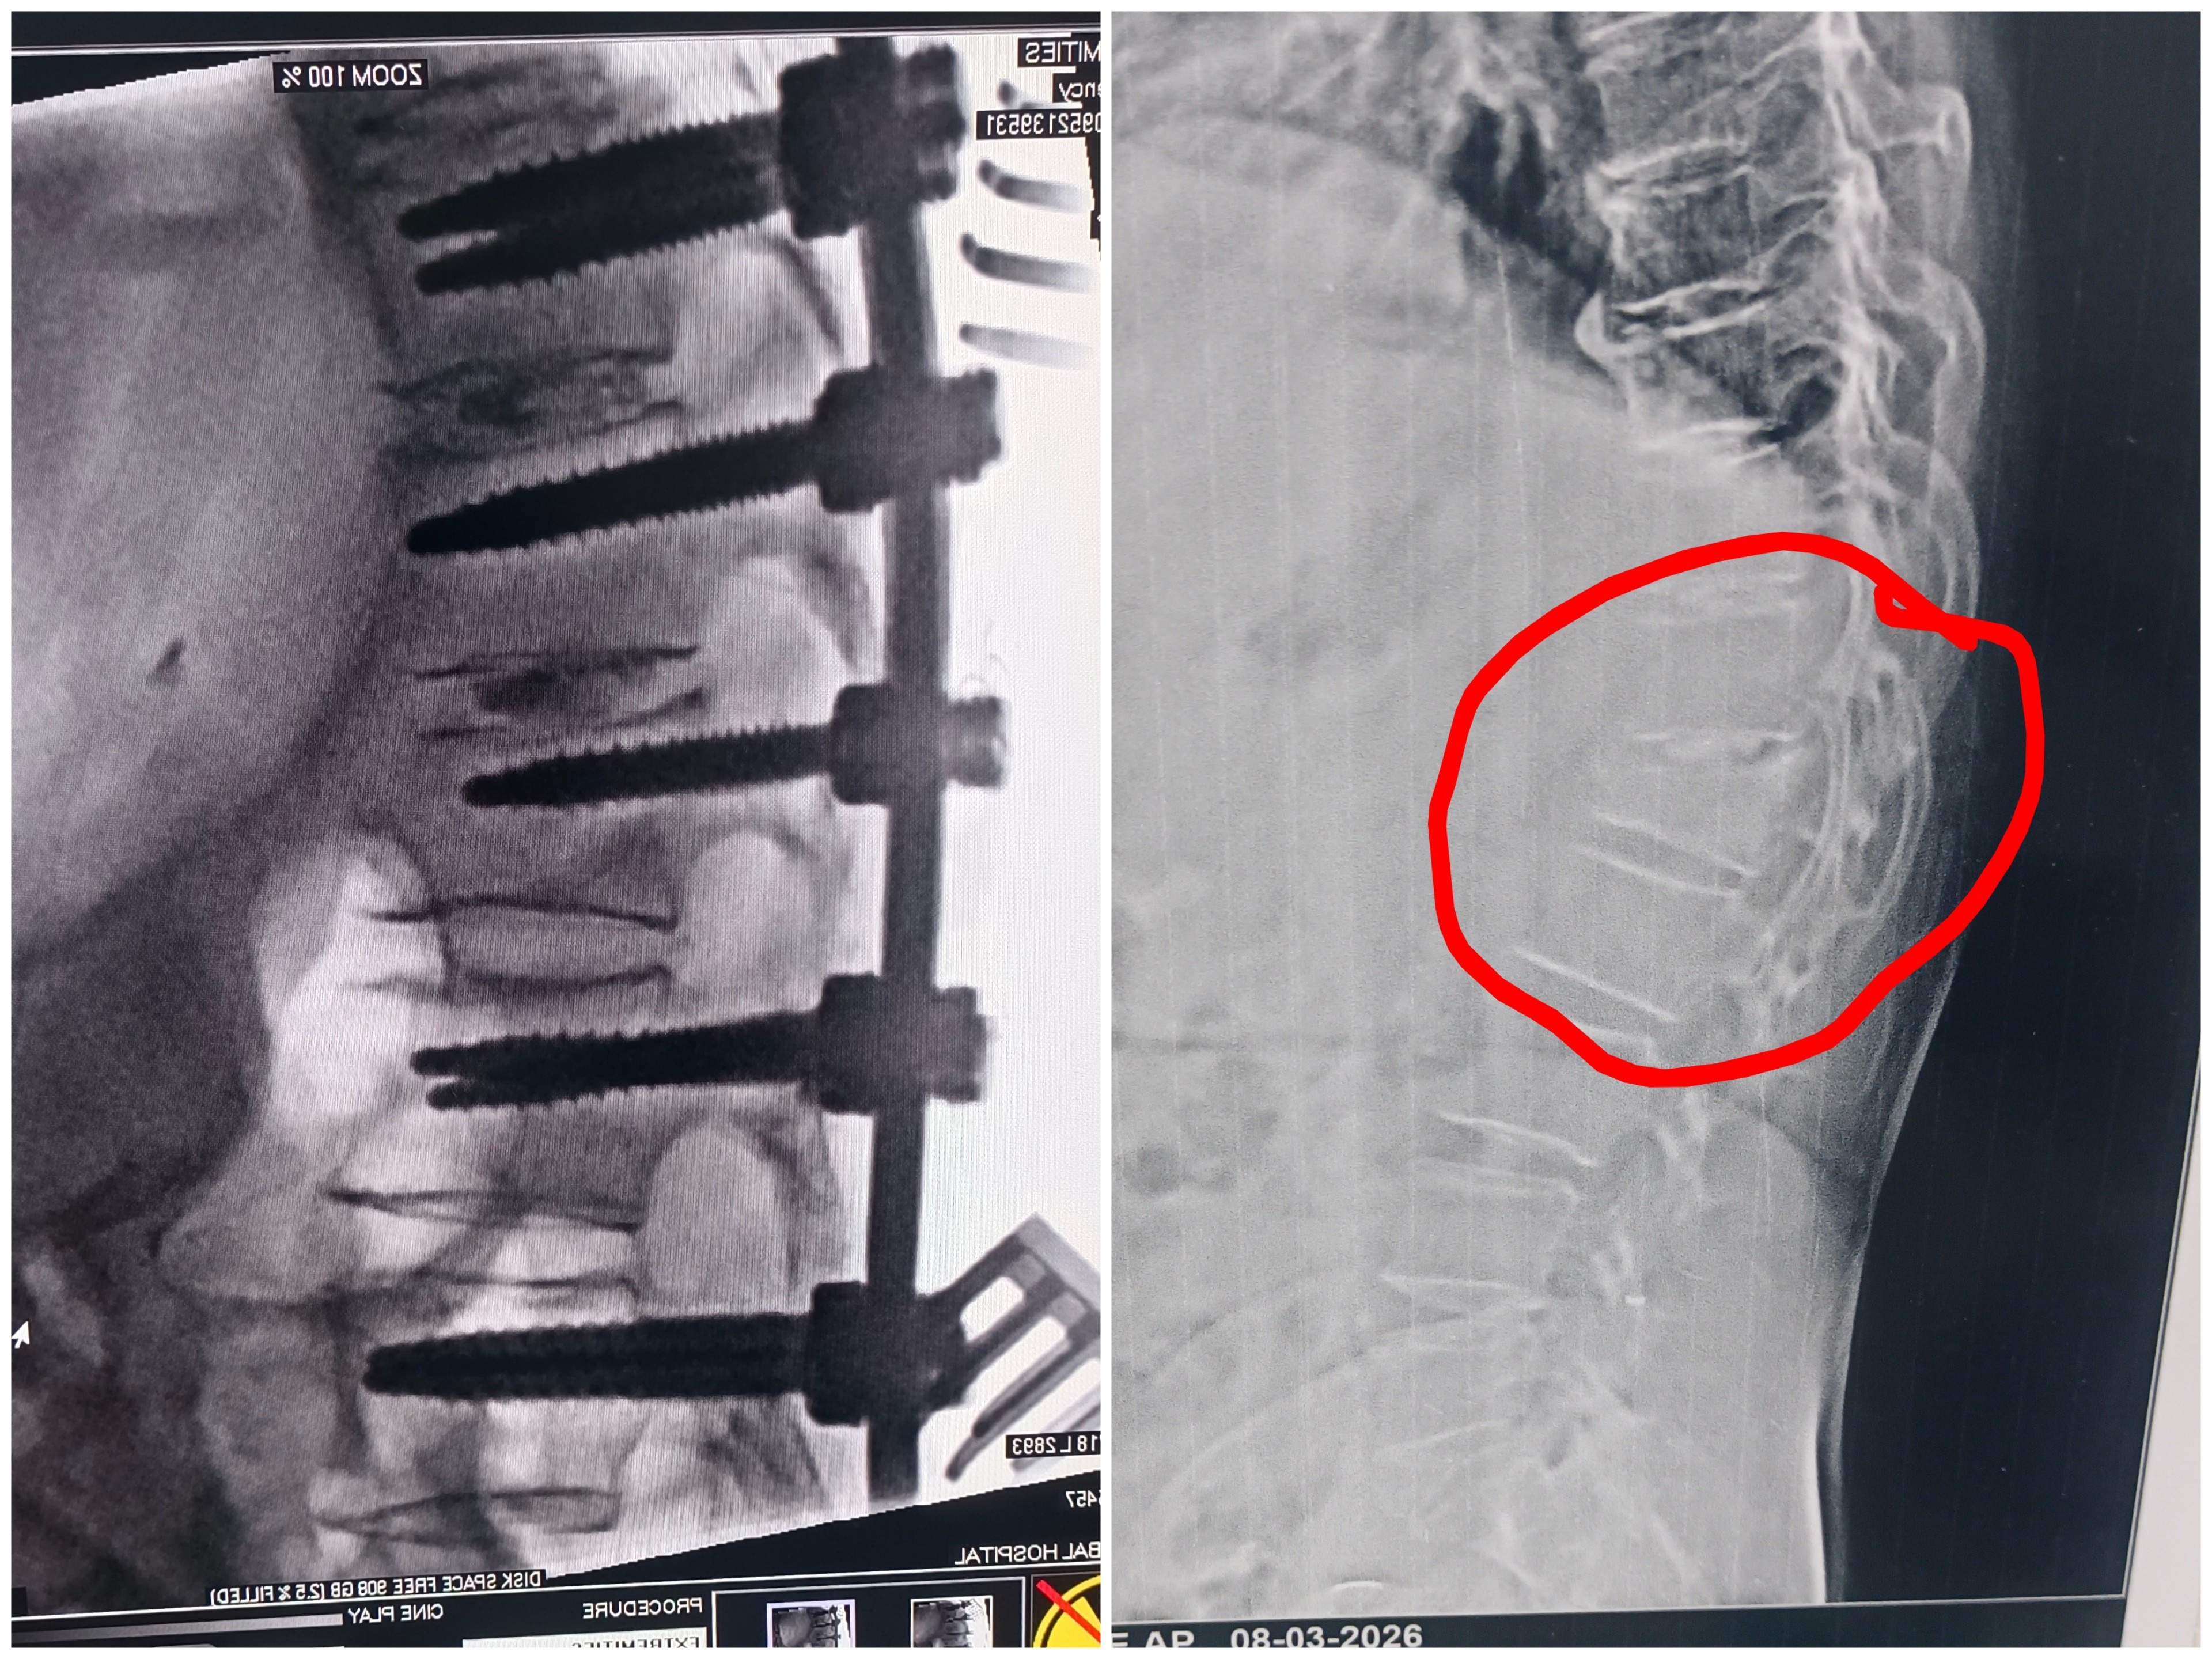

Are you searching for Spine Surgery Specialist in Pune ? Spine Surgery Doctor in Pune ? Spine Surgery Specialist In Shivaji Nagar ? Spine Fracture treatment in Pune ? Spine Fracture Surgeon in Pune ? Meet Dr. Nitish Agarwal Best Spine Surgeon in Pune, Shivaji Nagar, Deccan, Kothrud, Erandwane, Dattawadi, Swargate, FC road. This patient was bed ridden since 2 months after Major Fracture in her Spine. Her L1 vertebrae is collapsed due to fall. We did Spine Fixation Surgery for her by stabilizing her Spine with Titanium Screws and Rods. Patient starts walking from next day of Surgery. Now She is on her path of fracture healing and recovery.